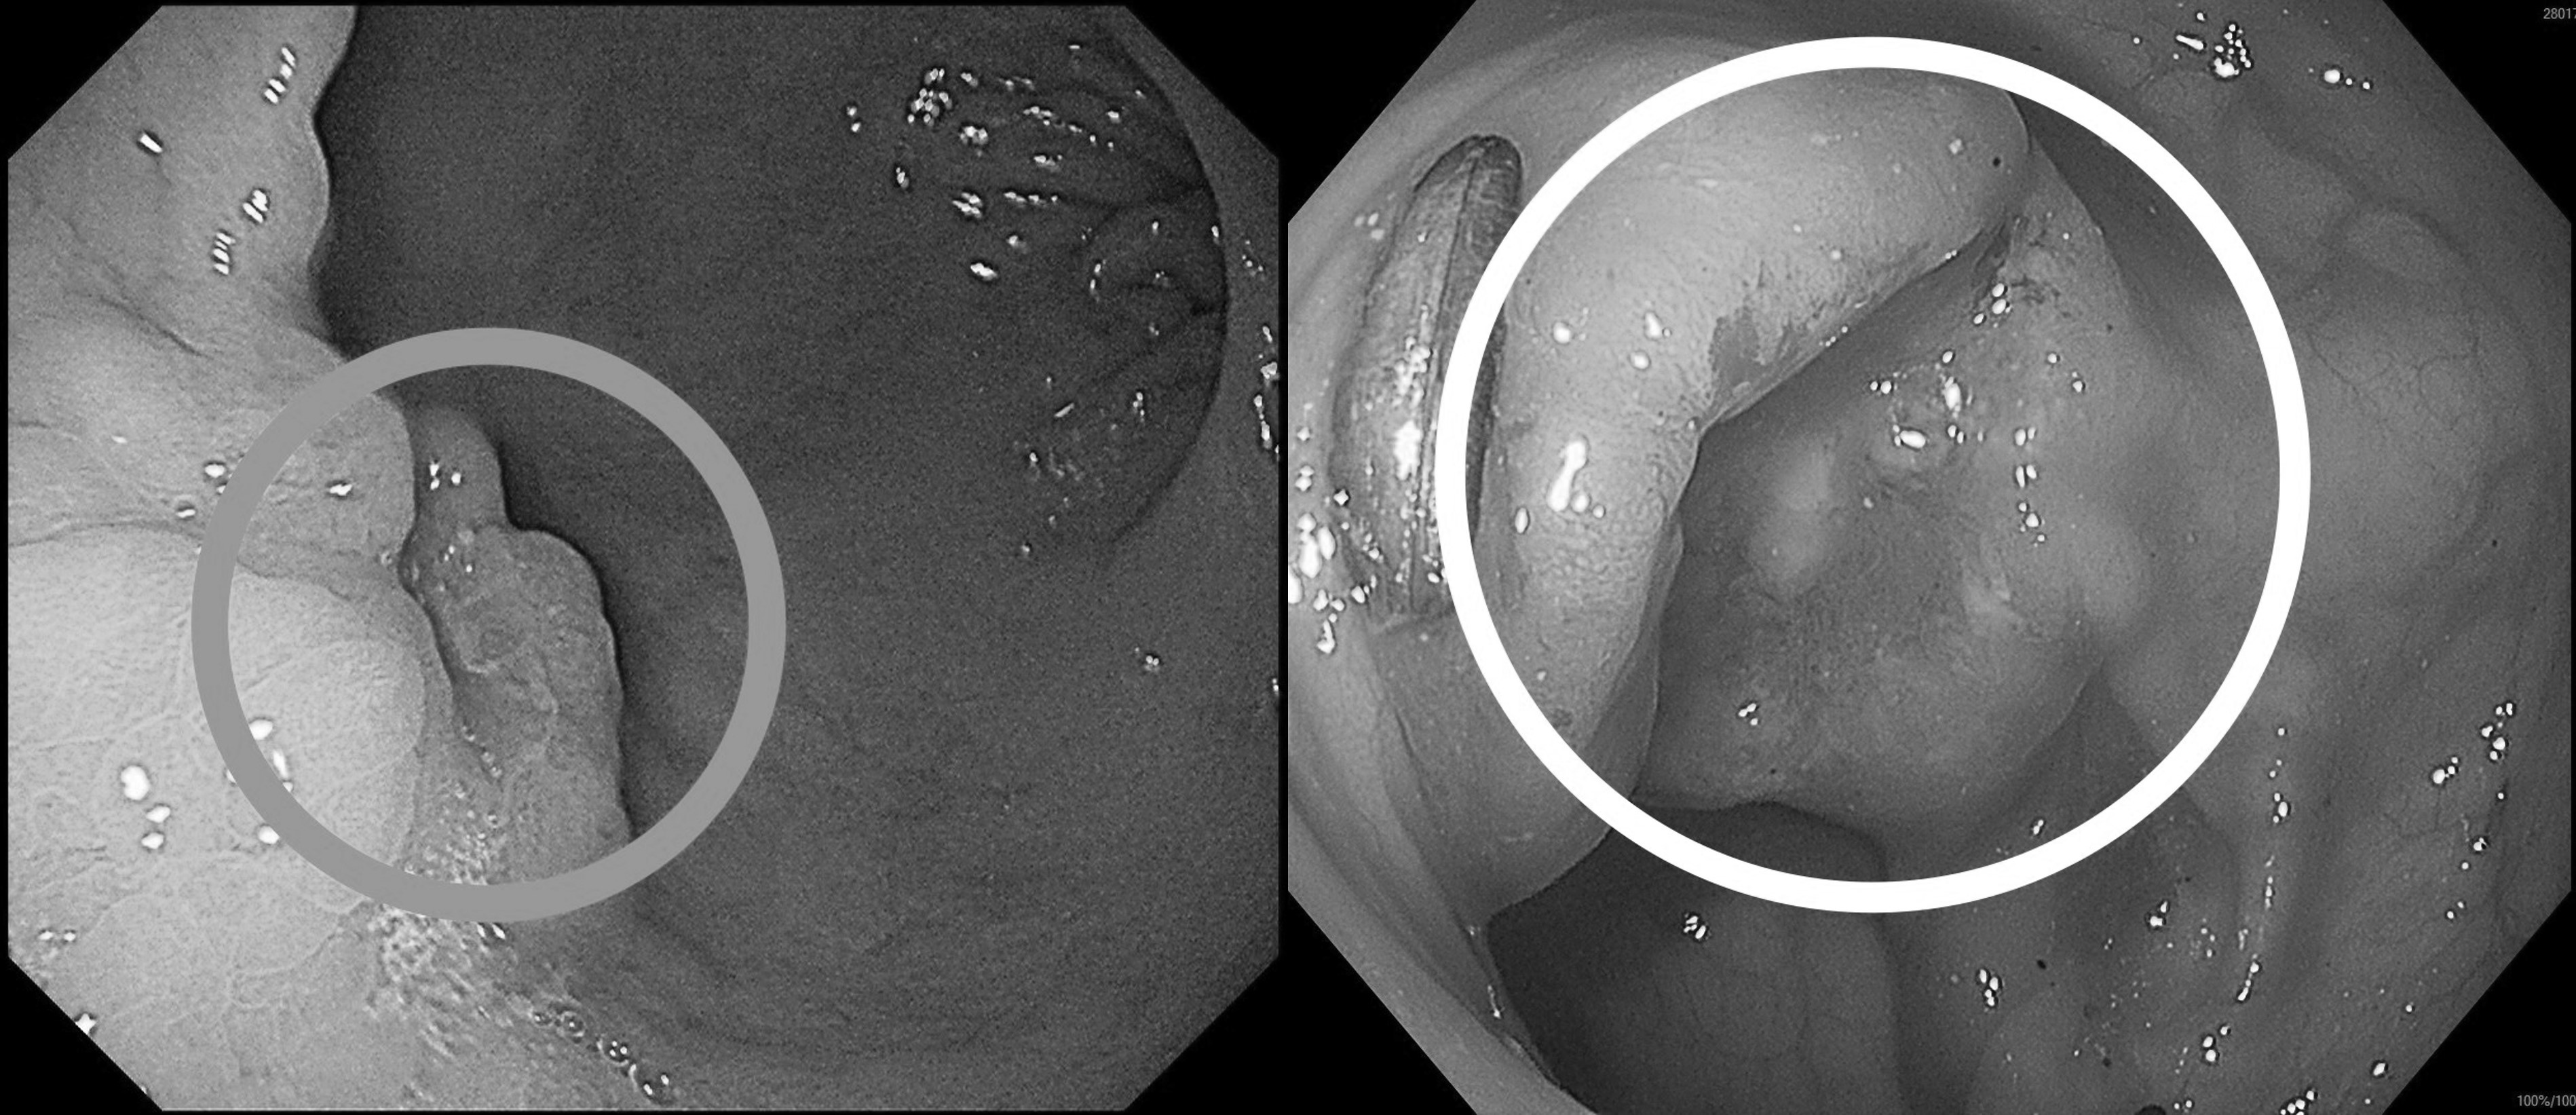

收治病人的高醫岡山醫院一般及消化系外科主任吳柏宣表示,張先生因突發上腹悶痛、糞便顏色變黑,由家人陪同到急診就醫。因懷疑有消化道出血,安排胃鏡檢查,在胃部發現兩公分惡性腫瘤,進一步做大腸鏡檢查,確認乙狀結腸也有一處3公分腫瘤,所幸兩處皆為可手術根治之病灶。